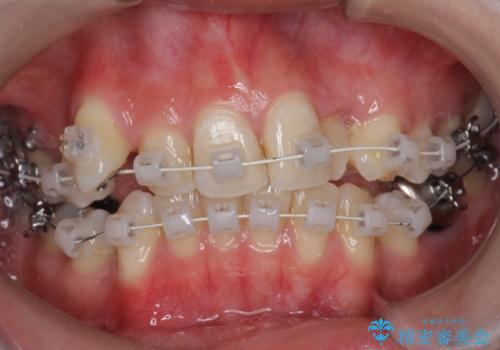

- 矯正装置

- ワイヤー矯正

- 前歯のがたつきを主訴に来院されました。

上の歯を2本抜歯して矯正しています。

また、右上の7番(一番後ろの歯)の状態が悪く、根尖病変がありました。根の治療をする選択肢もありましたが、歯質も薄く、予算的にも治療が難しかったため、抜歯して親知らずを並べています。